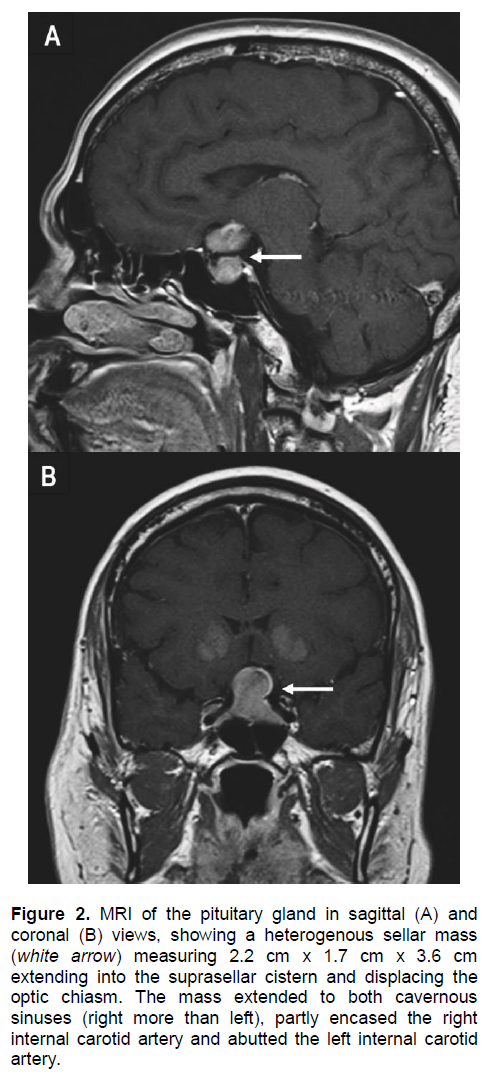

An urgent computed tomography (CT) scan of the brain revealed a suspicious sellar lesion together with bilateral head of caudate nucleus and basal ganglia calcification (Figures 1A and 1B). Magnetic resonance imaging (MRI) of the pituitary demonstrated a heterogeneous sellar mass measuring 2.2 x 1.7 x 3.6 cm extending into the suprasellar cistern displacing the optic chiasm. There was also extension to both cavernous sinuses (right more than left), partly encasing the right internal carotid artery and abuts the left internal carotid artery (Figures 2A and 2B).

Figure 2. MRI of the pituitary gland in sagittal (A) and coronal (B) views, showing a heterogenous sellar mass (white arrow) measuring 2.2 cm x 1.7 cm x 3.6 cm extending into the suprasellar cistern and displacing the optic chiasm. The mass extended to both cavernous sinuses (right more than left), partly encased the right internal carotid artery and abutted the left internal carotid artery.

It is reasonable to postulate lymphocytic hypophysitis (LYH) as the differential diagnosis of the pituitary lesion associated with the autoimmune primary hypopara-thyrodism. It is a rare autoimmune endocrine disorder of pituitary6 affecting women more frequently than men, with a male-to-female ratio of 1:8.7 The clinical features are very similar to pituitary adenoma which is the mass related effect,8 cranial diabetes insipidus9 and hypopituitarism. Our patient had presented with similar symptoms and the hormonal studies are suggestive of hypopituitarism. In pituitary MRI, patients with LYH usually show a pituitary enlargement with symmetrical suprasellar extension which can displace the optic chiasms, whereas patients with adenoma show asymmetrical pituitary enlargement. The pituitary stalk may be deviated in the adenoma but is usually thickened in LYH.10 The pituitary enhancement after injection of gadolinium is homogeneously intense in LYH and shows a strip of enhanced tissue along the dura madre (also called ‘dural tail’). Patients with adenomas instead show delayed and poor enhancement, usually without a dural tail after gadolinium.9 The asymmetrical enlargement of pituitary tumor demonstrated in our MRI pituitary (Figure 2) for this patient is more consistent with pituitary macroadenoma.